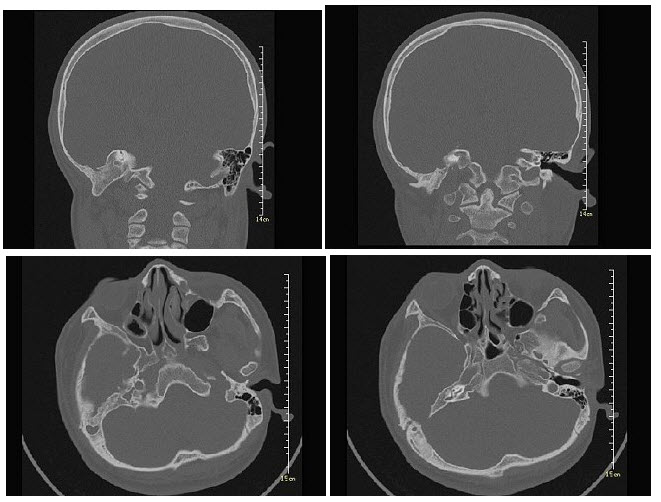

B.卵巢癌种植转移

女,12岁,自幼右侧听力丧失,CT检查如图,下列说法错误的是()

A.右侧外耳道闭锁

B.右侧外耳道不发育

C.右侧慢性化脓性中耳炎

D.右侧乳突为板障型

E.应诊断为先天性外耳道畸形